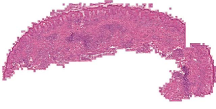

Curated dataset. Skin biopsies from 12 patients diagnosed with cutaneous leishmaniasis (spanning the disease differentiation spectrum) were acquired from Agha Khan University with Internal Review Board approval # 2024-9038-28175. Six of these biopsies, stained with hematoxylin & eosin (H&E), were scanned using Huron’s TissueScope digital scanner at 40X. A cheap-yet-clinical grade ($200) microscope (BS-2020MD Digital Microscope from BestScope International Limited, China) with a built-in digital 1.3 megapixel CMOS USB camera and 1W 5-LED illumination with Halogen Lamp 6V/20W was then used to capture videos for all 12 skin biopsies at 10X resolution. To show generalizability of our whole-slide image creation workflow for other common pathologies beyond cutaneous leishmaniasis, we also acquired videos for core biopsies of breast, liver, duodenum, stomach, and lymph node.

We demonstrate our WSI creation workflow on Leishmaniasis cases, as shown in Figures 1 and 4. An expert pathologist reviewed the cases and annotated granulomas as well as LD bodies on the stitched images and our generated images in Figure 4. To show generalizability of our approach, we also show results on core biopsies of breast, duodenum, stomach, liver, and lymph nodes (Figure 5).